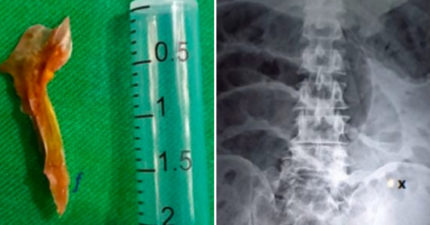

男腹痛送醫竟是「魚骨頭卡腸子」 8小時後身亡

September 24, 2022

世界